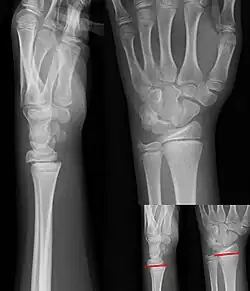

Salter–Harris I fracture of distal radius. -

Salter–Harris II fracture of ring finger proximal phalanx. -